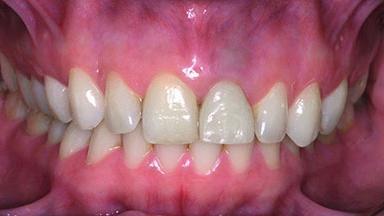

Replacement of a Perforated Upper Left Central Incisor: Early Placement of an RC Bone Level Implant

A 28-year-old patient presented at her general dentist’s office and complained about the appearance of her tooth 21. The patient had a history of trauma to this tooth. Endodontic treatment had been performed in the past and a crown placed on the tooth. A procedure to replace the old crown was performed by her dentist; however, a perforation on the middle third of the root occurred, and extraction of tooth 21 was suggested. Upon clinical and radiographic examination of the patient, who had been referred to us, replacement of tooth 21 by a dental implant appeared to be indicated.

Abutment Type Customized

Prosthesis Type FDP